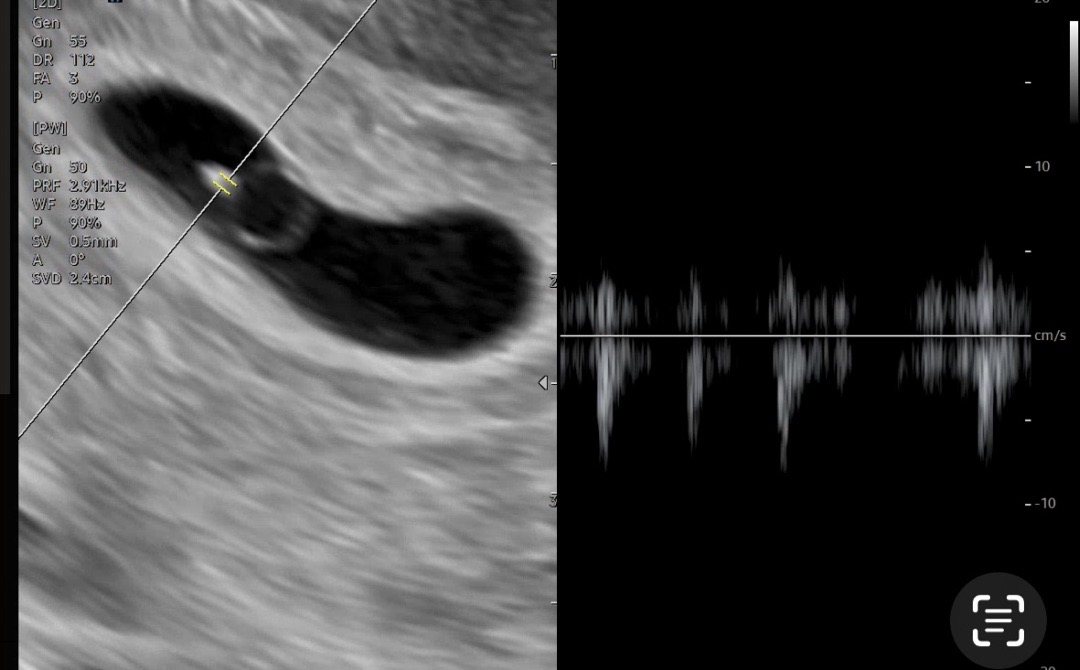

5주4일 심장소리 들었어요!

아침 병원가기 전에 쓰리라인 해보니 1번선이 진하게 나왔어요! 보통 5주차에는 심장소리 잘 못듣는다해서 기대를 좀 내려놓고 갔는데 아직 크진않지만 2미리 아기도 보이고 심장소리도 들었어요! 2주뒤에 오라는데 그 땐 젤리곰 볼 수 있겠죠? 이제야 뭔가 실감나네요 힣